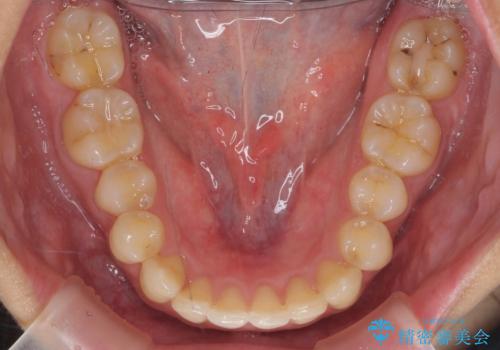

- 前歯の前突を主訴に来院。

かみ合わせが深く、また奥歯のかみ合わせも全体的に上が前にずれていました。

抜歯矯正も難しく、非抜歯矯正も歯の移動量が多くいずれにしても難易度が高い状態でした。

時間はかかりますが非抜歯で治療することにして、インビザライン矯正とワイヤー矯正を交互に行い仕上げました。

インビザライン矯正だけでなく、途中ワイヤー矯正もはさみました。前歯のかみ合わせが深く、本当に大変な治療でしたが協力度も高く非抜歯で上の奥歯を後ろに動かすことができました。